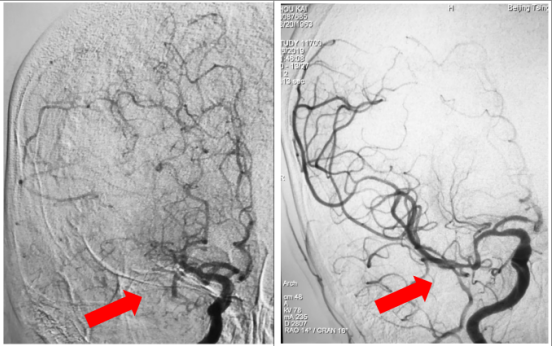

手术后:右侧大脑中动脉血流恢复通畅

取出栓子,左图第一次取数,右图第二次取栓

当天晚上,神经内科付伟亲自主刀,院总王也一助。手术用时1小时30分钟,全麻下,使用支架取栓+导管抽吸的“SWIM”技术,先后通过2次操作取出约4.0mm×2.0mm暗红色血栓,右侧大脑中动脉血流恢复,供血完全通畅。手术刚结束麻醉减量,病人意识转为浅嗜睡状态,病人的双侧肢体肌力全部恢复了!病人流利说话了!次日上午,患者去掉气管插管后意识已经恢复正常,肢体偏瘫症状也完全消失。患者顺利从ICU过度到了神经内科卒中单元病房,复查头部影像,患者脑梗死组织非常小,接下来的预后一定很不错。老周开心的比出大拇指,不断的感谢着绿色通道的所有医护工作者们。